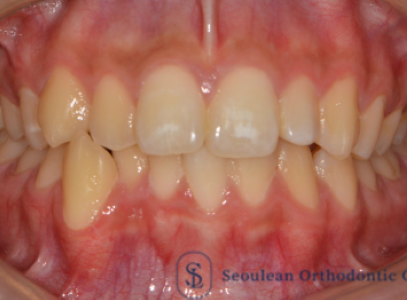

분당교정치과|10대 남학생 골격성 2급·돌출입, 제2소구치 발치교정으로 자연스러운 안모 개선